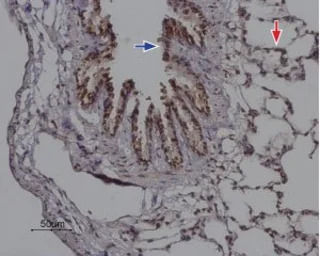

IHC-P analysis of rat lung tissue using GTX54767 ORAI2 antibody. Strong and specific staining is evident in bronchiolar epithelium (blue) and alveoli walls (red). Hematoxilin is used as the counterstain.

Dilution : 1:100